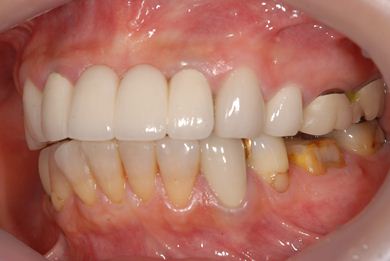

治療前

• 治療前

治療後

• 治療後